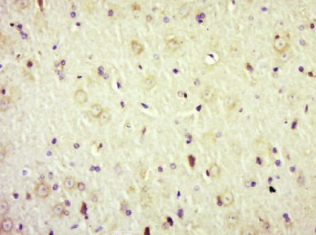

多聚甲醛固定,石蜡包埋(大鼠脑);经柠檬酸钠缓冲液(pH6.0)煮沸15min后获得抗原;用3%过氧化氢阻断内源过氧化物酶20分钟;阻断缓冲液(正常山羊血清)37℃30min;抗体(AdRa2)多克隆抗体(BS-1062R)在1:500过夜孵育。在4°C温度下,然后用共轭二次(SP-0023)进行20分钟的DAB染色。